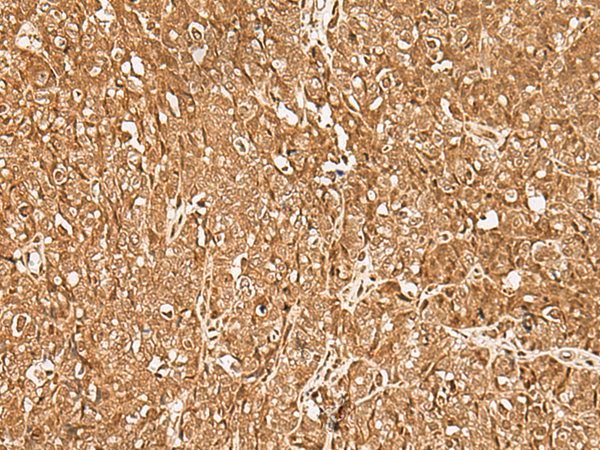

分类: 科研抗体货号: P06577别名: PIF79; GMEB-2; P79PIF应用: IHC反应种属: Human, Mouse, Rat